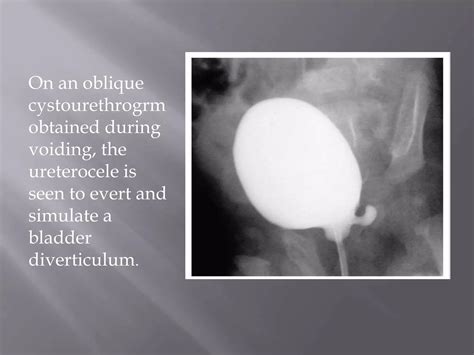

Voiding Cystourethrogram (VCUG) An X-ray procedure that shows the bladder filling and emptying; excellent for identifying diverticula.